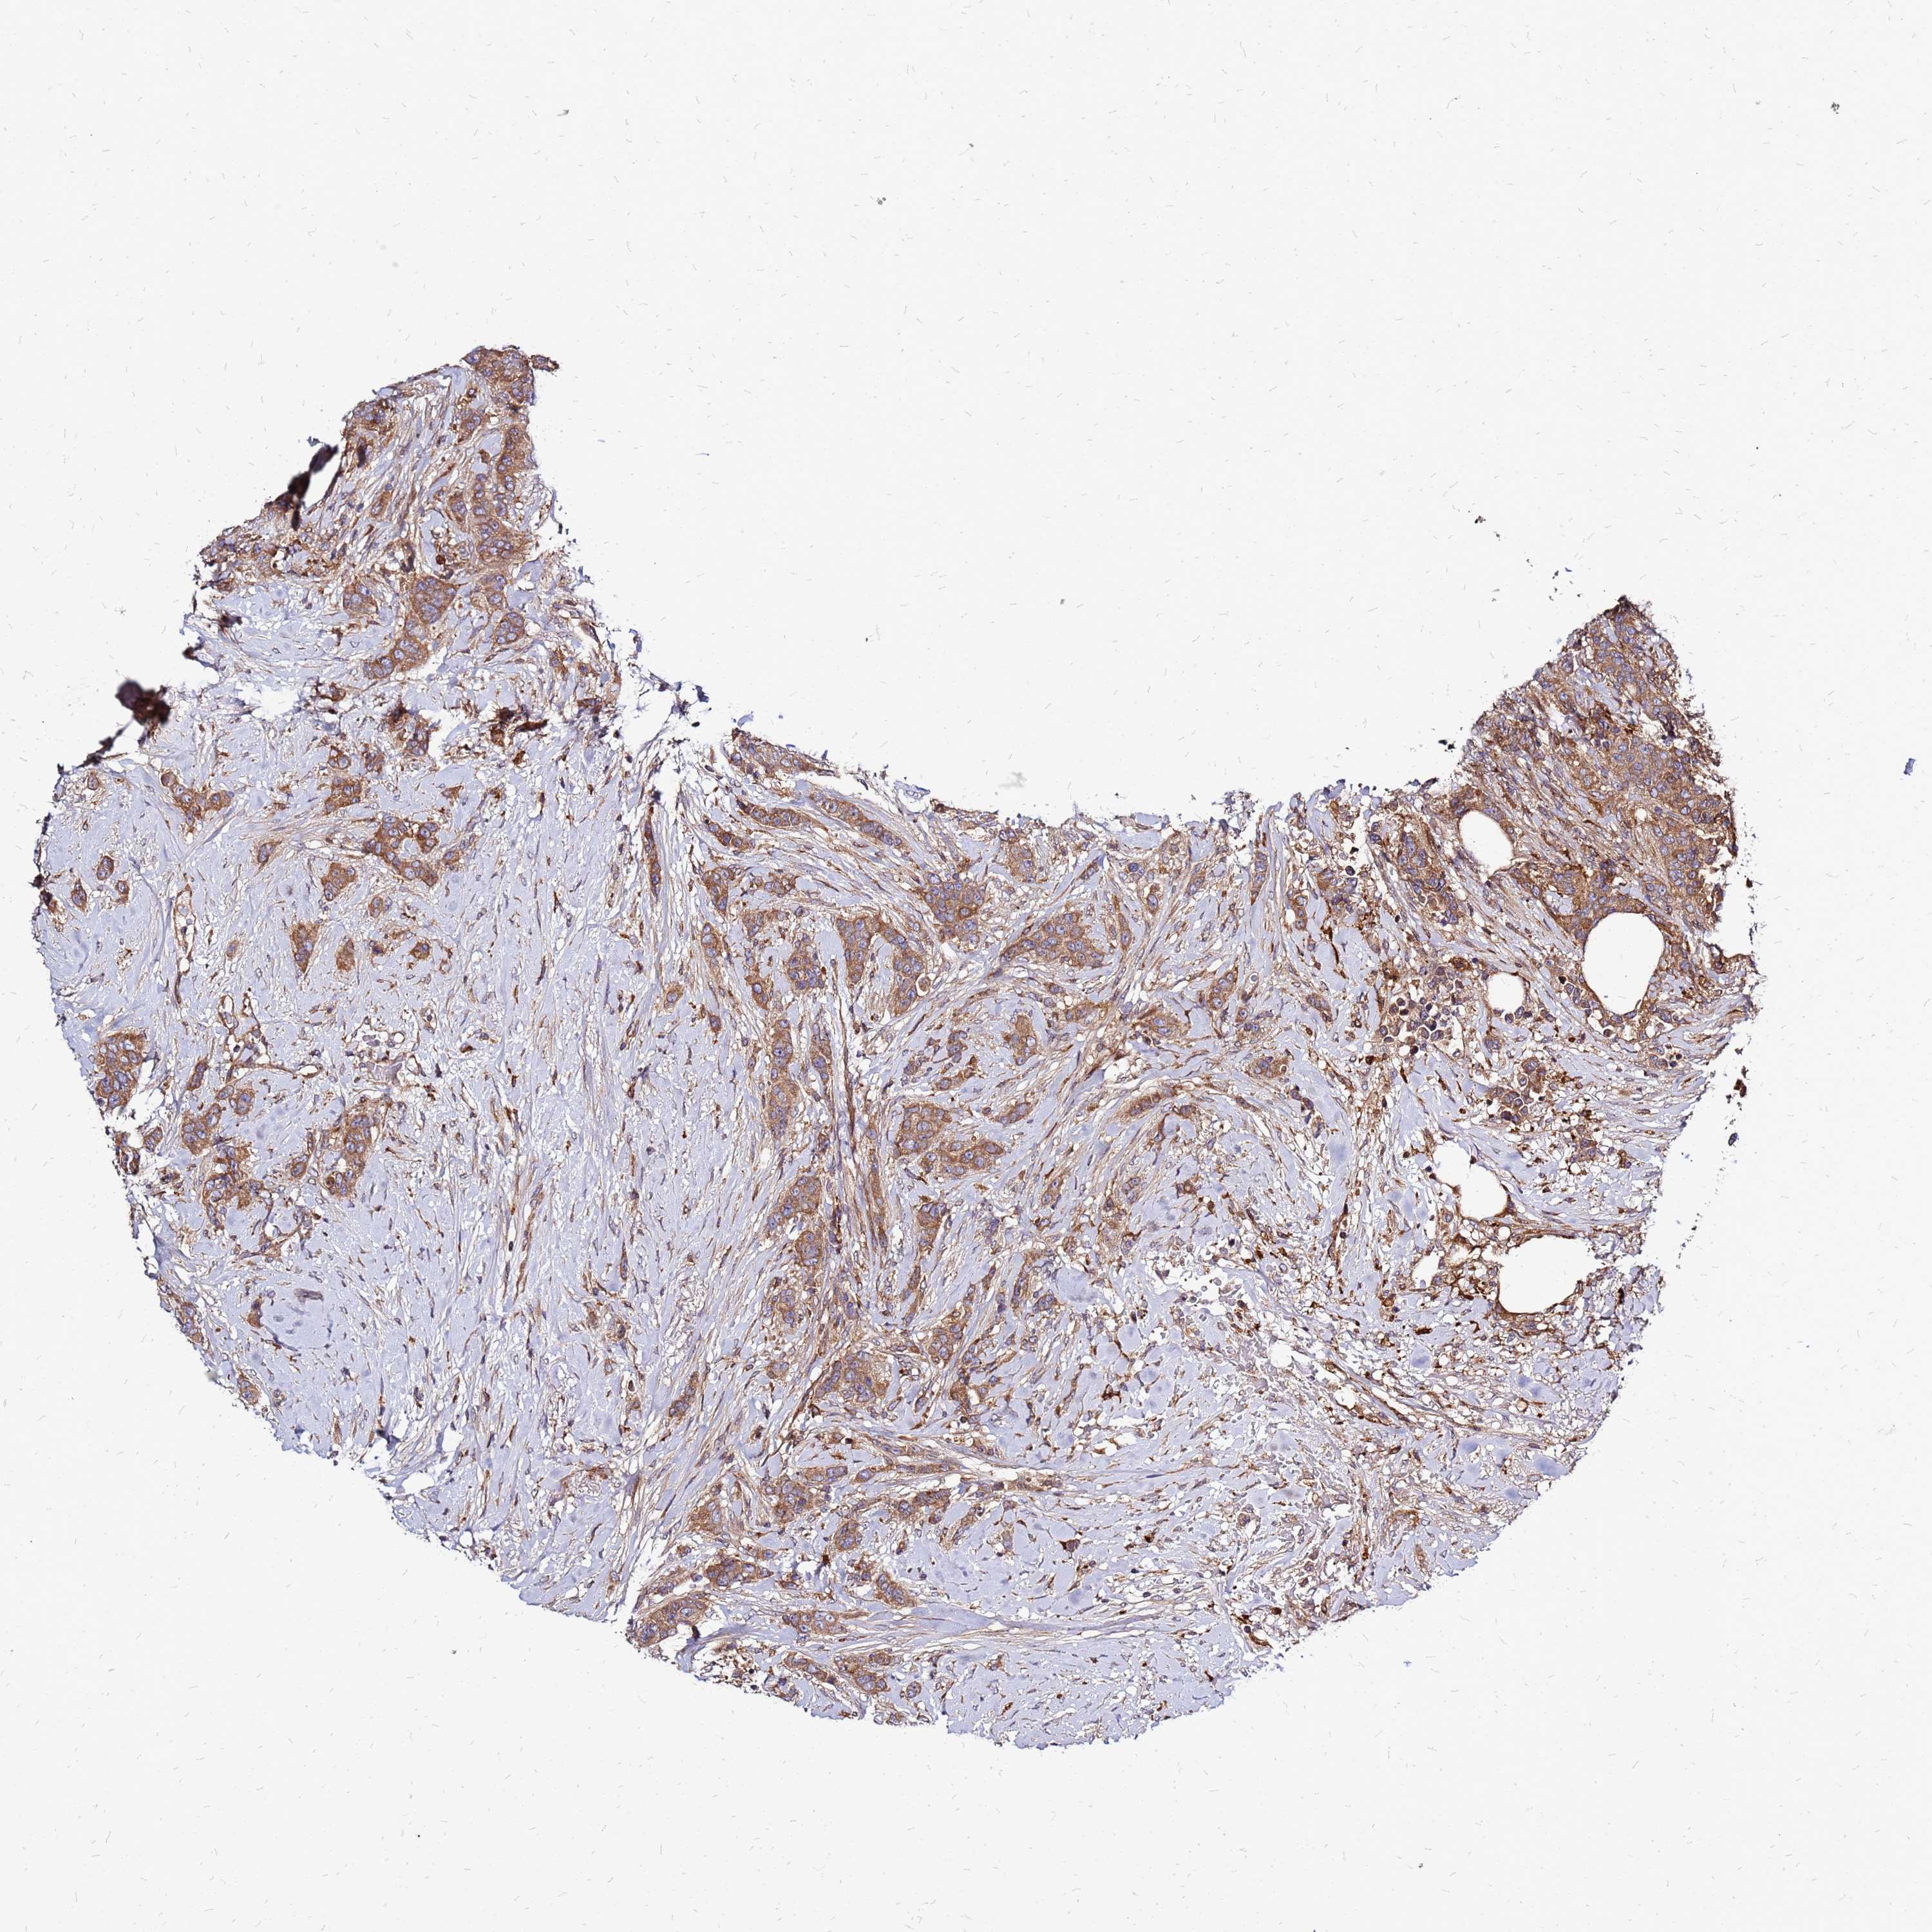

CANCER BREAST CANCER Show tissue menu

BRCA TCGA BRCA VALIDATION PROTEIN EXPRESSION